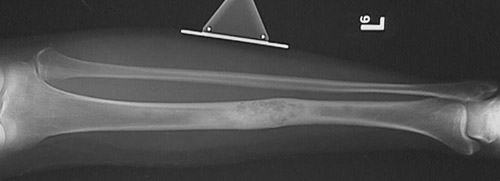

This is an

adamantinoma of long bone

, a rare neoplasm of bone seen here involving the mid-portion of the tibia.